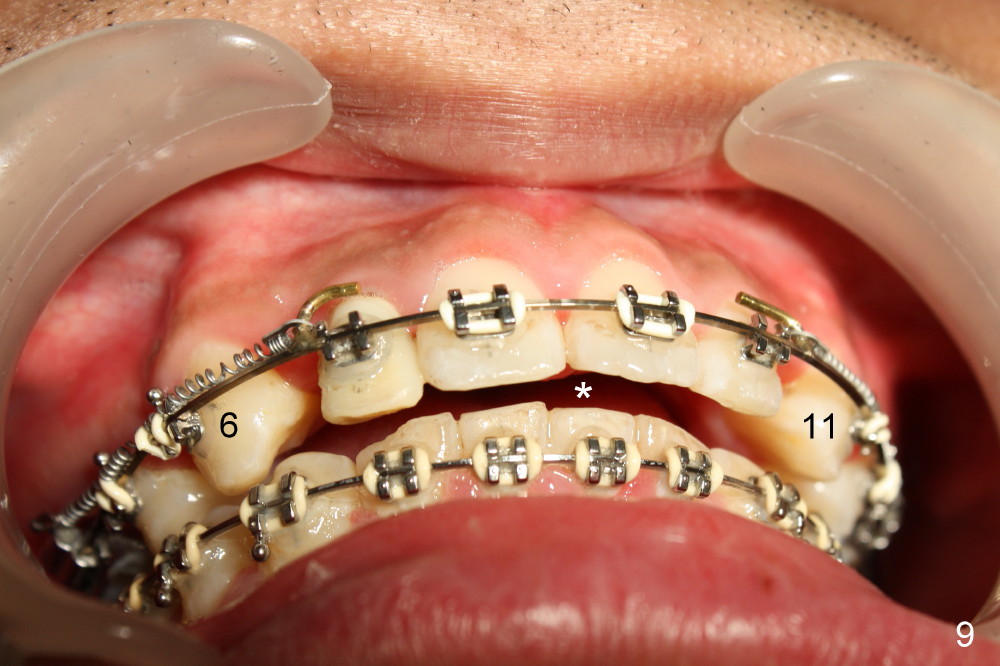

The 1st step of ortho is arch wire sequence to align the arches (from thin round wires to thick rectangular ones). The 2nd is to retract the canines distal (Fig.1 (planning), Fig.7 (6 months post bracketing), Fig.8 (7 months), using closed coil springs (*). The 3rd step is to move the remaining anteriors together distal using posted wire (^) and again closed coil springs (Fig.9; 8 month into treatment). Note the overjet between upper and lower anteriors (Fig.9: *). This space allows the upper incisors to move backward.